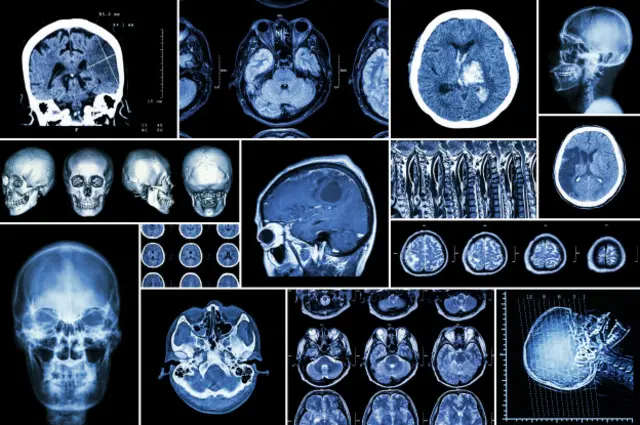

Crédito, ABr

"O vírus da zika e outros, como varicela, herpes vírus, enterovírus e até dengue, podem causar outros danos neurológicos – encefalites, cerebelites e neurites (inflamações no sistema nervoso) –, mas no cenário atual não está havendo grande aumento desses casosnovibet welcome offercrianças. Isso acontece talveznovibet welcome offer1% dos casos totais e geralmentenovibet welcome offerpacientes com baixa imunidade", diz a neuropediatra Maria Durce Carvalho, que acompanha casosnovibet welcome offermicrocefalia e outras infecções no Hospital Oswaldo Cruz,novibet welcome offerRecife.